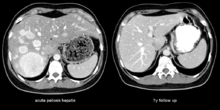

Peliosis hepatis is an uncommon vascular condition characterised by multiple randomly distributed blood-filled cavities throughout the liver. The size of the cavities usually ranges between a few millimetres to 3 cm in diameter.[1] In the past it was a mere histological curiosity occasionally found at autopsies but has been increasingly recognised with wide ranging conditions from AIDS to the use of anabolic steroids. It also occasionally affects spleen, lymph nodes, lungs, kidneys, adrenal glands, bone marrow and other parts of gastrointestinal tract.[2]